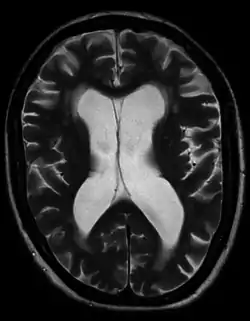

![]() МРТ пацієнта з доброякісною сімейною макроцефалією (чоловік з окружністю голови> 60 см) МРТ пацієнта з доброякісною сімейною макроцефалією (чоловік з окружністю голови> 60 см) | |

Доброякісна або сімейна макроцефалія

Доброякісна макроцефалія може виникати без причини або успадковуватися (при цьому вона вважається доброякісною сімейною макроцефалією і вважається мегаленцефальною формою макроцефалії). Діагноз сімейної макроцефалії визначається шляхом вимірювання окружності голови обох батьків та порівняння її з окружністю у дитини. Доброякісна та сімейна макроцефалія не пов'язані з неврологічними розладами[13], але нейророзвиток все одно оціненюється.

Хоча неврологічні розлади і не спостерігаються, можуть спостерігатися такі тимчасові симптоми, як: затримка розвитку, епілепсія та легка гіпотонія[13].